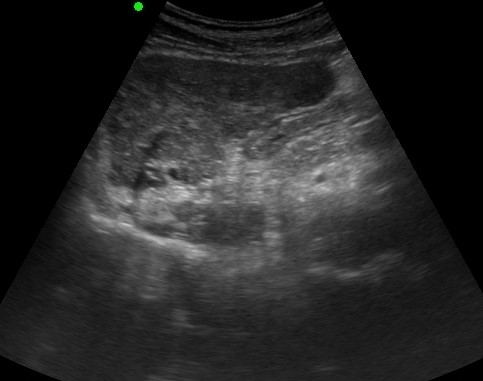

LIVER ) LC with RN & DN |

2019.05.11 мЎ°нҡҢмҲҳ: 214 |